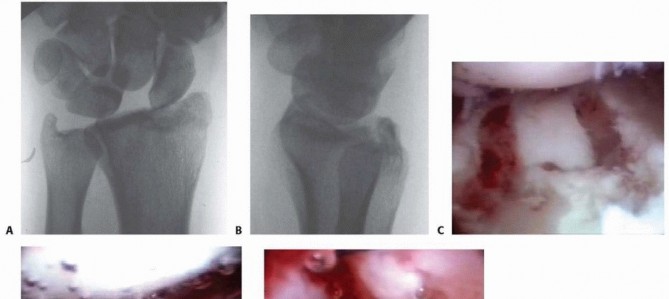

1. Attenuation/hemorrhage of interosseous ligament as seen from the radiocarpal joint. No incongruency of carpal alignment in the midcarpal space. There is a loss of the normal concave appearance between the carpal bones, and the interosseous ligament attenuates and becomes convex as seen from the radiocarpal space. In midcarpal space, the interval between the carpal bones will still be tight and congruent, with no step-off. Immobilization 2. Attenuation/hemorrhage of the interosseous ligament as seen from the radiocarpal joint. Incongruency/stepoff as seen from the midcarpal space. A slight gap between the carpal bones may be present. A slight gap (less than the width of a probe) between the carpal bones may be present. The interosseous ligament continues to become attenuated and is convex as seen from the radial carpal space. In the midcarpal space, the interval between the involved carpal bones is no longer congruent, and a step-off is present. In scapholunate instability, palmar flexion of the dorsal lip of the scaphoid will be seen as compared to the lunate. In lunotriquetral instability, increased translation between the triquetrum and lunate will be seen when palpated with a probe. Arthroscopic reduction and pinning 3. Incongruency/step-off of carpal alignment is seen in both the radiocarpal and midcarpal spaces. The interosseous ligament has started to tear, usually from volar to dorsal, and a gap is seen between the carpal bones in the radiocarpal space. A probe often is helpful to separate the involved carpal bones in the radiocarpal space. In the midcarpal space, a 2-mm probe may be placed between the carpal bones and twisted. Arthroscopic/open reduction and pinning 4. Incongruency/step-off of carpal alignment is seen in both the radiocarpal and midcarpal spaces. Gross instability with manipulation is noted. A 2.7-mm arthroscope may be passed through the gap between the carpal bones. The interosseous ligament is completely detached between the involved carpal bones. This is the “drive-through” sign, when the arthroscope may be freely passed from the radiocarpal space through the tear to the midcarpal space. Open reduction and repair In another study, SLIL injuries were found in more than half, LTIL injuries in one-third, and TFCC in 60%. Only 17% of patients were free of any of the three injuries. 28 Untreated complete tears of the SLIL, which are highly associated with radial styloid fractures, may progress to a wrist with scapholunate advanced collapse. ## PATIENT HISTORY AND PHYSICAL FINDINGS A thorough history should be obtained, including the circumstances surrounding the injury as well as any additional injuries. Neurologic basis Cardiac basis Patients' level of independence, dominant hand, status with assisted devices, work, activity level, and support structure should be determined. Physical examination, while concentrating on the wrist, should also include the hand, elbow, and shoulder to check for concomitant injuries. The hand, wrist, forearm, arm, and shoulder must be carefully inspected for open injury so that tetanus and antibiotic prophylaxis may be initiated if necessary. A thorough distal sensory and motor function examination should be carried out in an organized manner. Vascular examination should include palpation of both the radial and ulnar pulses and determination of capillary refill time. Precise palpation is used to define areas of potential trauma. Diminished sensibility, pallor, altered capillary refill, increased tenseness of the soft tissues, and pain out of proportion should raise suspicion for significant soft tissue injury, including compartment syndrome. ## IMAGING AND OTHER DIAGNOSTIC STUDIES Posteroanterior (PA), oblique, and lateral radiographs are the primary radiographic studies used to workup distal radius fractures. Radiographs of the uninvolved contralateral extremity are useful to compare radial inclination, ulnar variance, and sigmoid notch anatomy. PA projections are useful to evaluate the radial inclination, radius height, presence of ulnar styloid fractures, widening of the DRUJ, widening of intercarpal spaces, and intra-articular involvement ( FIG 1A). Standard radiographic parameters of the distal radius include radial inclination of 22 degrees (range 13 to 30 degrees), radius length of 12 mm (range 8 to 18 mm), and volar tilt of 11 degrees (range 1 to 21 degrees). Ulnar variance should be measured with the shoulder in 90 degrees of abduction, the elbow at 90 degrees of flexion, and the wrist in neutral pronation-supination. A lateral projection is used to assess volar and dorsal tilt of the distal fragment, dislocation or subluxation of the DRUJ or carpus, lunate angulation, and dorsal comminution ( FIG 1B). ![]() |

| * FIG 1 • A. PA radiographic view showing a minimally displaced radial styloid fracture fragment. B. The lateral view shows a complete fracturedislocation of the wrist. A modified lateral radiograph with the beam angulating 10 to 30 degrees proximally improves visualization of the articular surface and evaluation of the volar rim of the lunate facet represented by the anterior teardrop. An additional 30-degree anteroposterior (AP) cephalic projection is useful to evaluate the dorsal ulnar margin of the distal radius. Oblique radiographs are very helpful because major fracture fragments may be rotated out of their anatomic planes. Computed tomography (CT) evaluation, particularly threedimensional CT, can further delineate fragment location, joint compression, and rotation. Magnetic resonance imaging (MRI) evaluation is useful in assessing for associated soft tissue injuries such as TFCC tears, interosseous ligament injuries, and carpal fractures. Radiographic signs that demonstrate that the distal radius fracture is likely unstable and closed reduction would be insufficient include the following 21: Lateral tilt greater than 20 degrees dorsal Dorsal comminution greater than 50% of the lateral width Initial fragment displacement greater than 1 cm Volar translation greater than 2 mm Initial radius shortening more than 5 mm Intra-articular step-off greater than 2 mm Associated ulnar fracture Severe osteoporosis Age older than 60 years ## DIFFERENTIAL DIAGNOSIS Carpal bone fracture Metacarpal or phalangeal fracture DRUJ disruption Essex-Lopresti lesion Interosseous ligament tear Carpal dislocation (perilunate) ## NONOPERATIVE MANAGEMENT Displaced fractures of the distal radius are reduced using an adequate anesthetic agent. Knowledge of the mechanisms of injury helps facilitate manual reduction. Force is applied opposite the force that caused the fracture. Gentle traction is necessary to disimpact the fracture fragments, followed by palmar translation of the hand and carpus in respect to the radius. The radius articular surface will rotate around the intact volar cortical lip to restore volar inclination with palmar translation. Care must be taken to avoid trauma to the skin during the reduction maneuver, particularly in elderly patients where the skin may be fragile. A splint is supplied following the reduction. No consensus has been established regarding wrist or forearm position, longarm versus short-arm immobilization, or splint versus cast. Extreme positions of wrist flexion and ulnar deviation should be avoided. Postreduction radiographs are taken in plaster. Depending on stability of the fracture, most patients treated nonoperatively require weekly visits for the first 3 weeks to monitor fracture reduction. In patients older than 65 years, one-third of initially undisplaced fractures subsequently collapsed to some degree. One study of elderly patients with moderately displaced fractures of the distal radius found that two-thirds of the correction obtained by closed manipulation was lost at 5 weeks. Patients with minimally displaced or nondisplaced fractures of the distal radius treated nonoperatively must be made aware of possible complications, including rupture of the extensor pollicis longus tendon, carpal tunnel syndrome, and compartment syndrome. Elderly patients typically tolerate nonoperative management well. Patients older than 65 years undergoing nonoperative results have comparable results to those that undergo operative treatment despite unsatisfactory radiographic outcomes. 2, 3 ## SURGICAL MANAGEMENT Distal radius fractures without extensive metaphyseal comminution are ideal candidates for arthroscopic- assisted fixation with K-wires or cannulated screws. 14, 15, 22 Radial styloid fractures Impacted fractures Die-punch fractures Three-part T-type fractures and four-part fractures with metaphyseal comminution are best treated with a combination of volar plate stabilization. Wrist arthroscopy is used as an adjunct to fine-tune the articular reduction and evaluate for associated soft tissue lesions. Distal radius fractures that may be minimally displaced, and fractures with strongly suspected associated soft tissue injury, also are candidates for arthroscopic-assisted fixation to stabilize the fracture but, more importantly, to evaluate and treat the acute associated soft tissue injury. Stabilization of associated ulnar styloid fragments is controversial. 20 Wrist arthroscopy provides a rationale as to when to stabilize an ulnar styloid fragment. ## Preoperative Planning All radiographic studies are reviewed. Equipment needed for arthroscopic treatment and for open stabilization is made available. Small joint instrumentation is essential for arthroscopicassisted fixation of distal radius fractures. The small joint |

TECH FIG 1 • A. Arthroscopic view of the patient whose radiographs are seen in FIG 1. The arthroscope is in the 6R portal looking across the wrist, and a blunt trocar is in the 3-4 portal. The displaced radial styloid fragment is well visualized. B. A combination of joysticks inserted into the radial styloid fragment and a trocar inserted into the 3-4 portal allows anatomic reduction of the displaced radial styloid fragment and radiocarpal joint. C. The radial styloid fragment is anatomically reduced (with no residual rotation) and stabilized. D. PA view demonstrating anatomic reduction to the radial styloid fragment. Headless cannulated screws are used, if possible, to avoid soft tissue irritation. E. Lateral view showing anatomic restoration to the radial styloid fragment and restoration of the carpus in line with the radius. Suspend the wrist in a traction tower and establish the standard arthroscopic portals. Insert the scope in the dorsal 3-4 portal and clear the joint of debris and hematoma. Transfer the arthroscope to the 6R or 4-5 portal to look across the wrist and effectively judge rotation and reduction of the radial styloid fragment. Using the previously placed guidewires as joysticks, manipulate and anatomically reduce the fracture fragment under direct arthroscopic observation. A trocar can be inserted through the 3-4 portal to help further guide the reduction of the radial styloid fragment ( TECH FIG 1A,B).